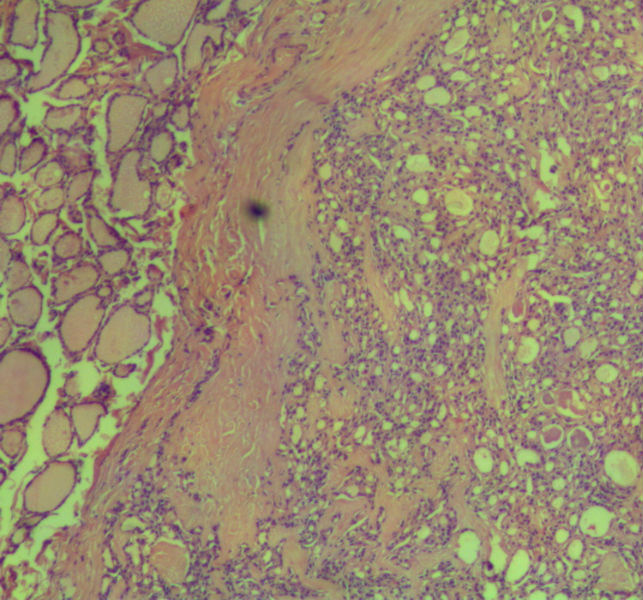

女,45岁,体检发现颈前区一结节,术中送检甲状腺左腺叶,发现一界清结小1*0.8cm,灰黄色。术中诊断滤泡性肿瘤伴包膜累及,局部疑包膜穿破,滤泡癌可能,待石蜡报告。石蜡连续切片形态见图,可见明显包膜穿破,诊断为滤泡性癌。患者借片到上级医院会诊,结果为:包膜内滤泡癌伴包膜累及。请问有包膜内滤泡癌的提法吗?这个病例怎么诊断啊?请各位老师多指导。

• 这个是滤泡性癌吗图1

图1

甲状腺滤泡癌确实分2型:浸润型包膜不完整,明显浸润周围甲状腺组织;包裹性血管浸润型有包膜,但有血管或包膜浸润。

本例包膜不完整,应该是滤泡癌。